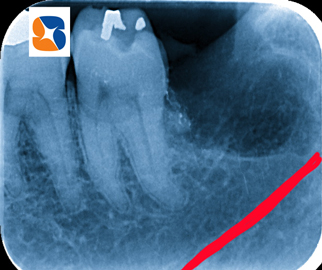

〈抜歯前の診断〉

①歯の頭の部分…もろもろに崩壊しているため、掴んで引っ張り出す抜歯法が出来ない。

②歯の根の部分…あご骨に横向きで埋まっているため、歯肉や骨に隠れて歯が見えない。